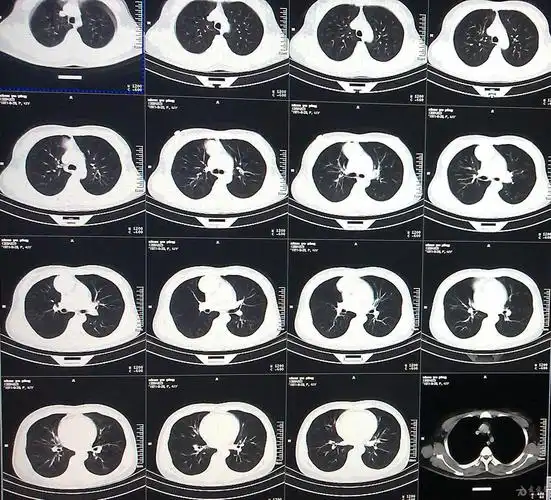

新病人在排除新冠,ct影响考虑?感染,占位? [病例帖]

女性,无任何自觉症状,体检肺ct平扫 增强

3月22日当地卫生院胸部ct

外院ct平扫